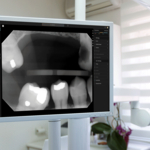

Pearl’s system supports dental professionals in their review of radiographs by applying computer vision to identify and highlight key pathologic and nonpathologic findings, including dental caries, discrepancies at the margin of existing restorations, calculus, periapical radiolucency, crowns, fillings, root canals, bridges and implants. When x-rays are captured in a dental office, Second Opinion® immediately displays the images and any detected conditions on monitors in the operatory, giving dentists sharper vision into their patients’ oral health and giving patients greater understanding of their dentist’s findings.

Second Opinion® exceeded the FDA’s stringent efficacy requirements across four separate clinical studies, each featuring a radiographic dataset of over 2,000 images and a reader group of 86 expert dentists and dental radiologists. The tests showed clear advantages for readers using Second Opinion®, including finding that study participants reading x-rays with the assistance of Pearl’s AI system accurately identified 36% more lesions than those without AI assistance did.